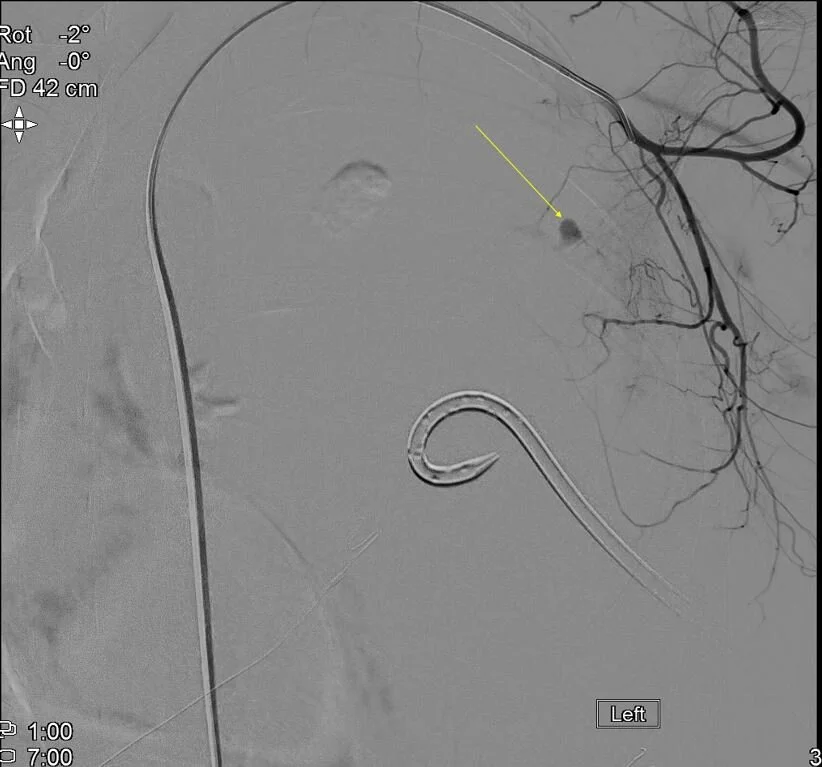

Angiogram confirms bleeding aneurysm. This was embolized.